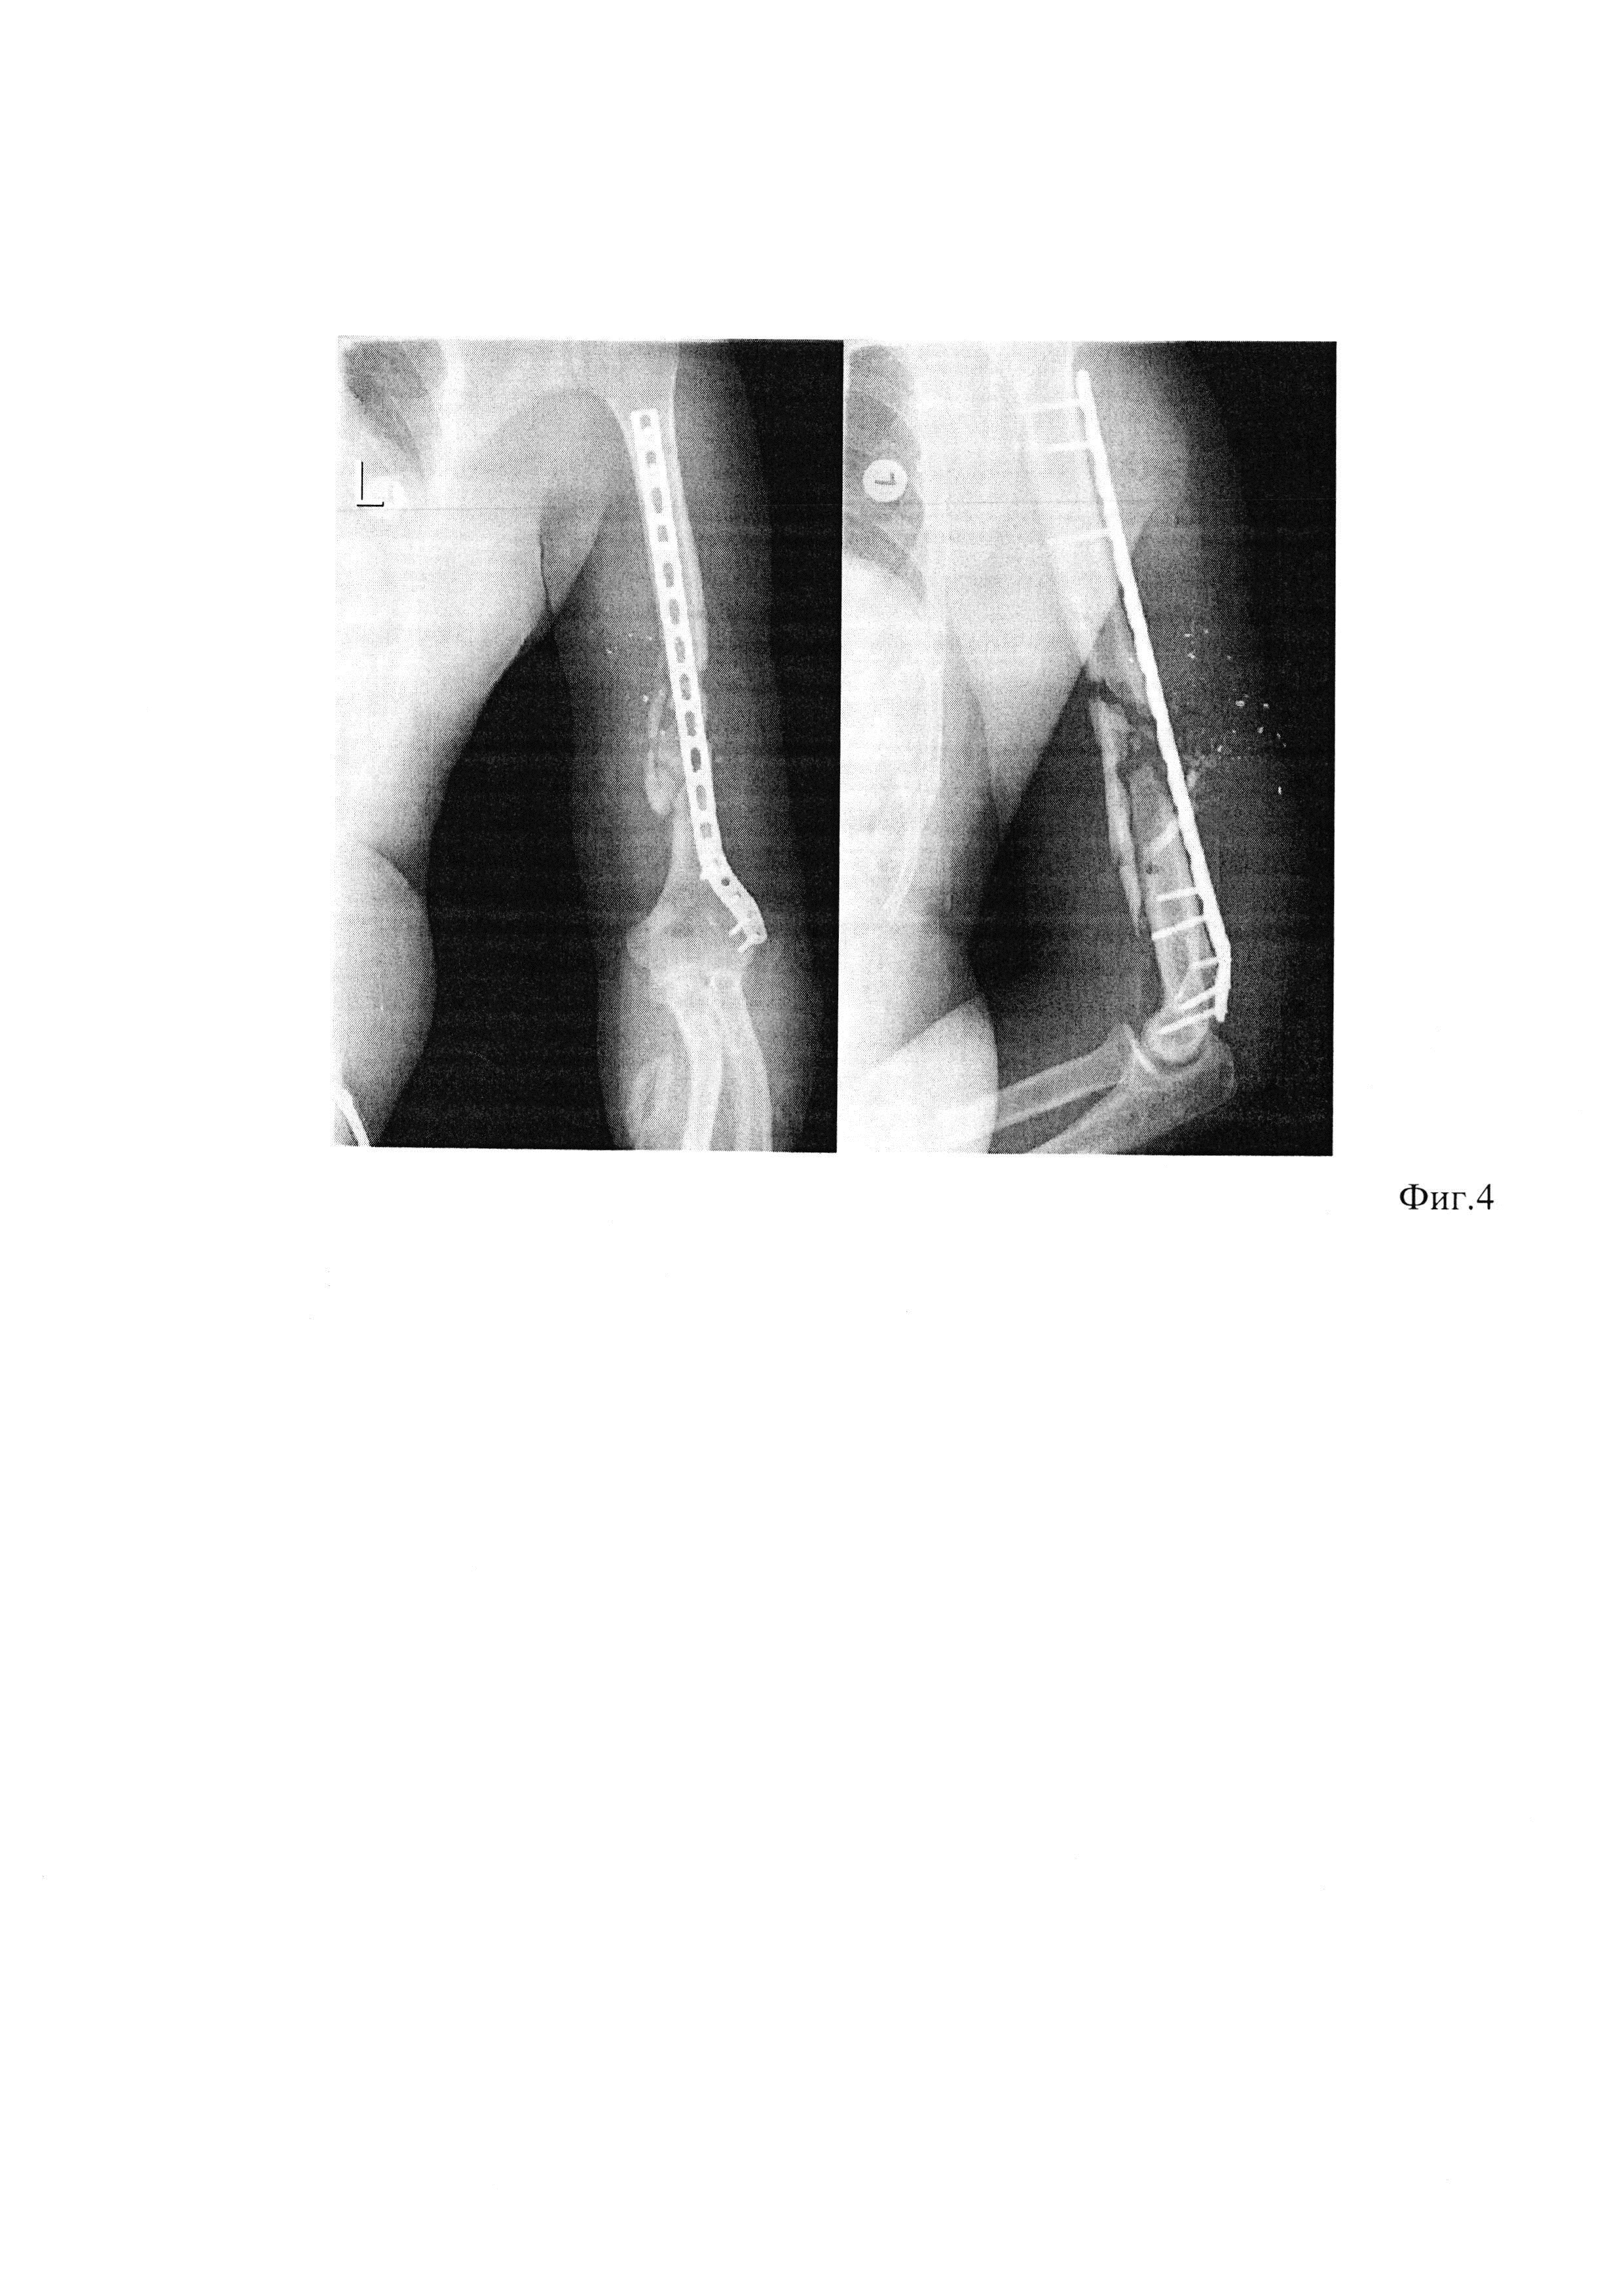

[12]

Фиг. 1. Рентгенограммы левого плеча, на котором определяется многооскольчатый перелом плечевой кости в нижней трети со смещением отломков. Левая плечевая кость фиксирована внешним аппаратом из комплекта стержневого военно-полевого (КСВП) на 4-х стержнях.

[25]

На одном из этапах медицинской эвакуации пострадавшему выполнена операция: первичная хирургическая обработка ран левого плеча, фиксация левого плеча аппаратом КСВП (фиг. 1 А, Б). Через 2 суток после ранения пациент доставлен в клинику военной травматологии и ортопедии ВМедА. При обследовании выявлено огнестрельное осколочное сквозное ранение левого плеча с огнестрельным многооскольчатым переломом плечевой кости в нижней трети со смещением отломков (фиг. 1 А, Б). В клинике раненому ежедневно выполняли перевязки ран правого плеча с мазью левомеколь, получал комплексное консервативное лечение, а именно: антибактериальную терапию широкого спектра действия, анальгетики. Пострадавшему на 6 сутки после поступления выполнен первично отсроченный шов ран левого плеча. На 18-е сутки после поступления в клинику отмечено заживление огнестрельных ран мягкотканого покрова левого плеча. Через 3 недели от момента ранения выполнена операция: демонтаж аппарата КСВП, закрытая репозиция, минимально-инвазивный остеосинтез левой плечевой кости пластиной с угловой стабильностью винтов (фиг. 3, 4). В послеоперационном периоде на протяжении трех недель проводили иммобилизацию оперированной конечности косыночной повязкой. Активные движения в плечевом и локтевом суставах начинали со вторых-третьих суток после операции по стиханию болевого синдрома.